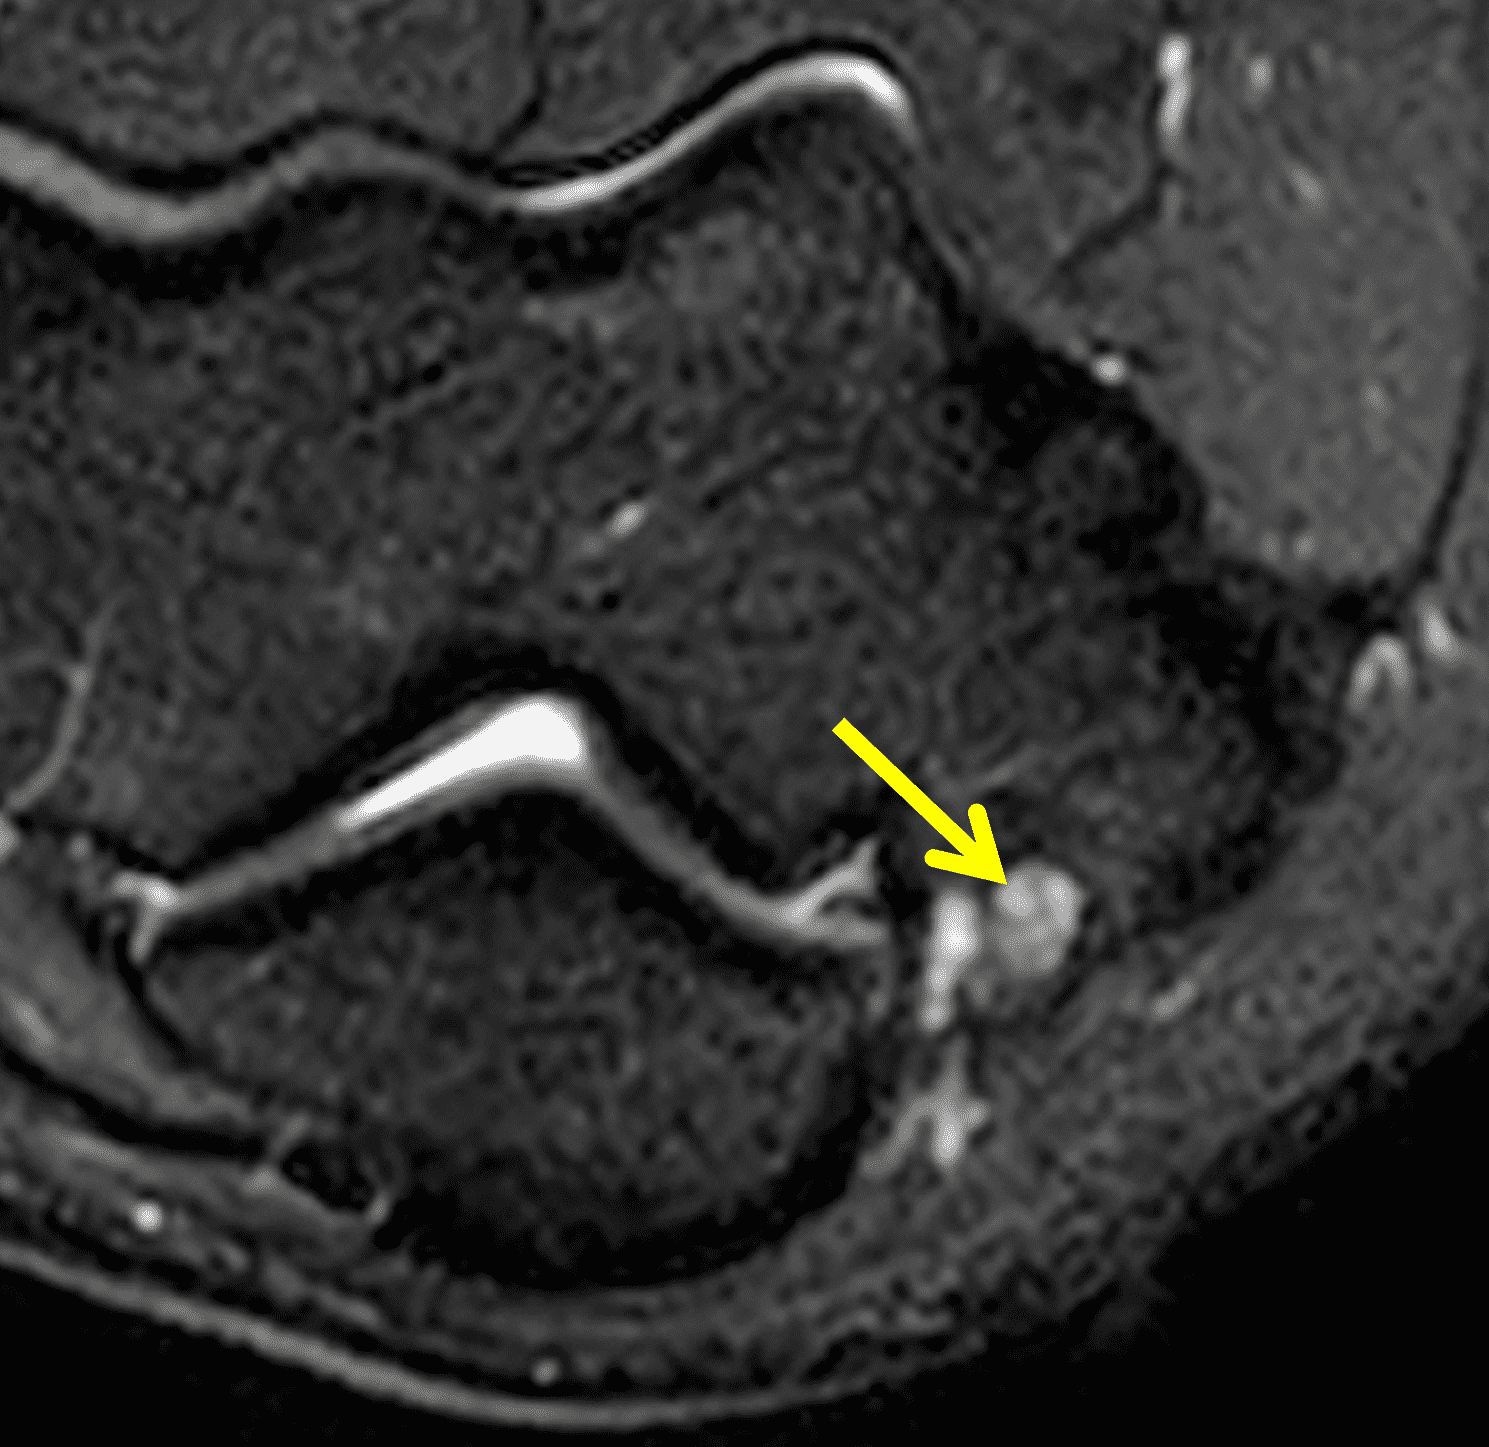

Figure 7: Absent cubital tunnel retinaculum. (7A) Drawing depicts absence of the retinaculum overlying the cubital tunnel contents. Compare with Figure 3B. (7B) Axial T1-weighted image with the elbow extended shows a normally-positioned ulnar nerve (arrow) with no defined retinaculum extending from the olecranon to the medial epicondyle. In the same patient with the elbow flexed, (7C) T1-weighted and (7D) fat-suppressed, fluid-sensitive images demonstrate dislocation of the ulnar nerve (arrows) relative to the medial epicondyle (ME).